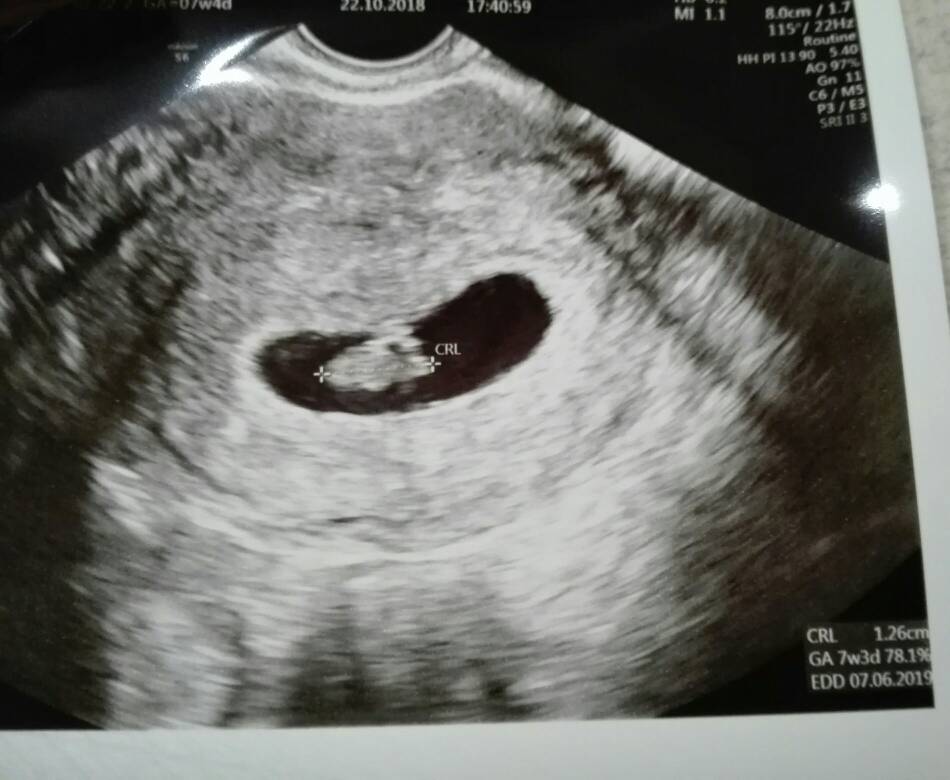

Cudownie :* ja.jutro wrzucę USGCześć dziewczyny [emoji7] jestem przeszczesliwa, moja dzidzia ma 1,26cm i pieknie bijace serduszko [emoji7][emoji7]

Mam porobic badania i za niecale dwa tygodnie kolejna wizyta [emoji7]

Wzruszylam sie jak pokazalam mlodemu zdjecie usg jak wypytywal gdzie dzidzius jak duzy jest i co tam w brzuchu robi [emoji28] [emoji7] a potem tztowi pokazywał gdzie jest dzidzia [emoji7][emoji173][emoji173]Zobacz załącznik 909927